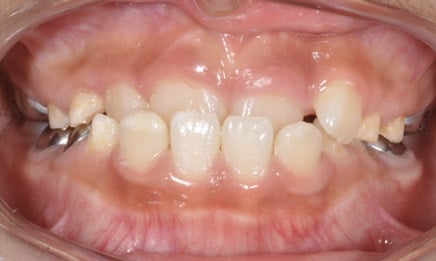

This is around the time when permanent teeth are coming in and it is important to evaluate if an early round of braces is necessary. Most orthodontic treatment at this age is for correcting significant “bite” issues, such as crossbites and openbites, but it can also be important to discuss thumb sucking and other important issues that will affect a child’s dental development.

Some kids have need for 2-phase orthodontics. Although this is rare (only 10% of kids at Dental Town), it is a very important and significant round of treatment. Phase I and Phase II are typically broken down as such:

Phase 1: Kids (ages 7-10)

Beginning treatment in this phase allows us to watch the jaw as it develops to make sure it is growing in a way that will accommodate permanent teeth and improve the patient’s bite.